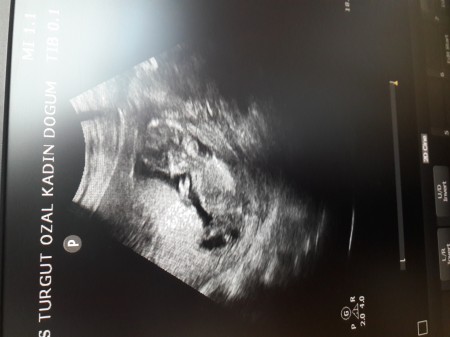

Kızlar bugün kontrole gittim bebegimin ilk resmi 14 haftalıgım ama cinsiyeti söylemediler tahmini olan varmı

Gebelik haftası 14 haftalık